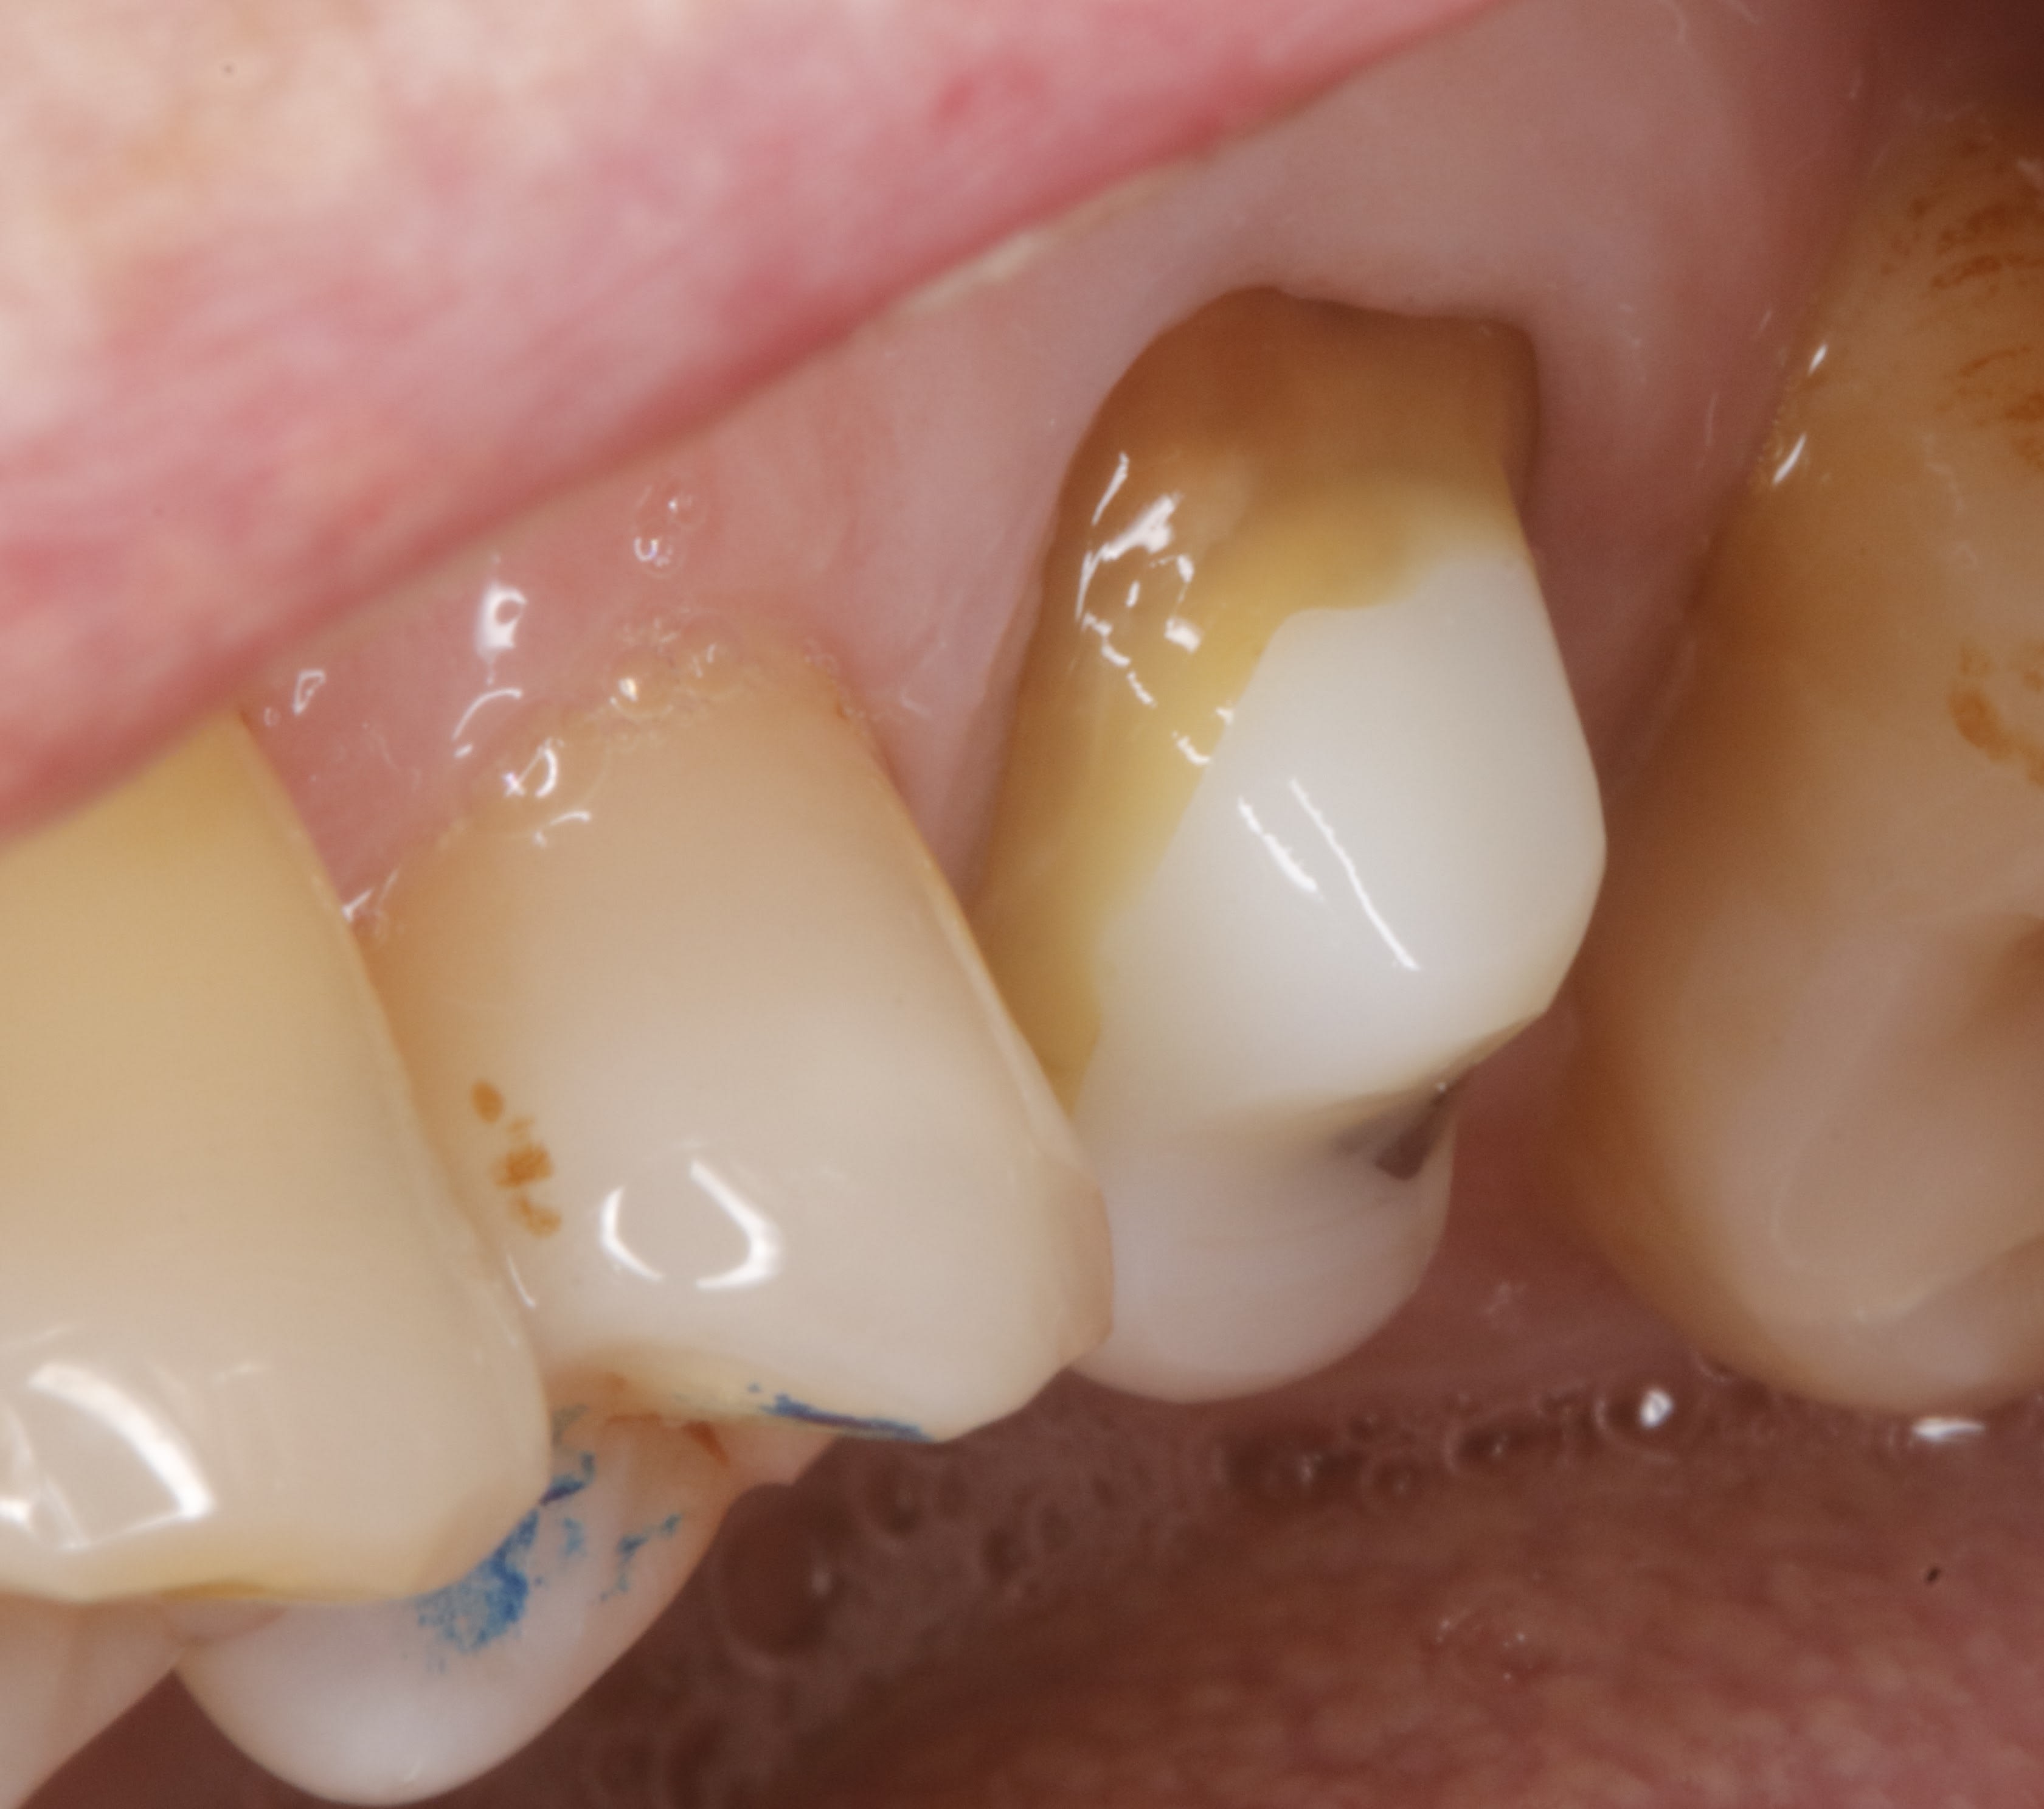

une dernière d aujourd'hui .

le cas de départ était profond pour un jeune . il est resté des mois avec son pansement et ça saigne volontiers

et le plus simple était de couper la papille emboucanée et là on est à 3 semaines sans prov , aujourd'hui c est le jour de la pose .

la photo de ce matin , c est le jour de l empreinte limites retaillées .